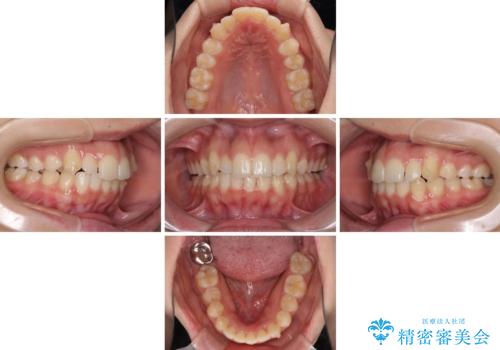

- 前歯のデコボコと八重歯を気にして来院された患者様です。

叢生の程度は中等度であったため、IPR(歯と歯の間を削る)と歯列の側方拡大をメインに、インビザラインを用いて歯列を改善することとしました。

また、下顎骨の右側変位による右側臼歯の咬合を改善させるよう試みることとしました。

右側の咬合改善を目標に様々な手法を用いましたが、骨格的なズレによる不正咬合はインビザラインでは改善することができませんでした。